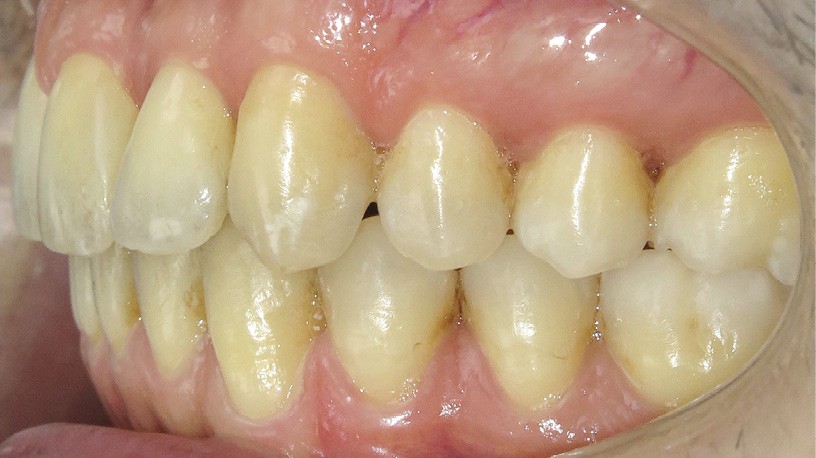

Discussion (fig. 5a- i)

La difficulté a été de garder le patient motivé, car les trois temps du traitement se sont ajoutés (2,5 ans) et le traitement reposait beaucoup sur sa coopération (dispositifs amovibles à savoir les élastiques et les gouttières).

Cependant, le patient est récompensé des choix qui ont été faits, car désormais son sourire est harmonieux avec une occlusion équilibrée. L’augmentation des triangles noirs a été limitée grâce aux soustractions amélaires au niveau des faces proximales des dents antérieures. En revanche, pour parfaire le résultat au niveau esthétique, des apports de composites ont été réalisés, car les dents de devant étaient très pincées au niveau cervical.

Le traitement est stable dans le temps, car les contacts occlusaux sont harmonieux ainsi que les fonctions et les déplacements ont été surtout coronaires.